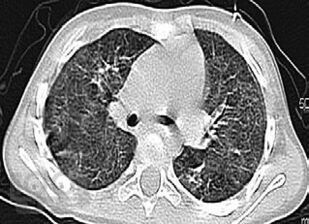

Монография посвящена актуальной теме интерстициальных болезней легких в детском возрасте, многие из которых являются редкими болезнями с тяжелым течением и неблагоприятным прогнозом. В связи с этим своевременная диагности ка и терапия этих болезней необходимы для предотвращения ранней инвалидизации и предотвращения смертности пациентов. Особое внимание уделено гиперсенситивному пневмониту, который в последние годы встречается в педиатрической практике чаще других. В монографии нашли отражение интерстициальные поражения легких при наследственной патологии, диффузных заболеваниях соединительной ткани, системных васкулитах, лекарственных поражениях, болезнях накопления, легочных геморрагиях. Обсуждаются также подходы к проблеме ИБЛ у детей раннего возраста.

В книге обобщены современные данные литературы о различных клинических вариантах ИБЛ, со многими из которых авторам непосредственно пришлось иметь дело в практической деятельности на протяжении не одного десятка лет, и, которые представляют наибольший интерес и важность с точки зрения встречаемости и клинической значимости в детском возрасте.